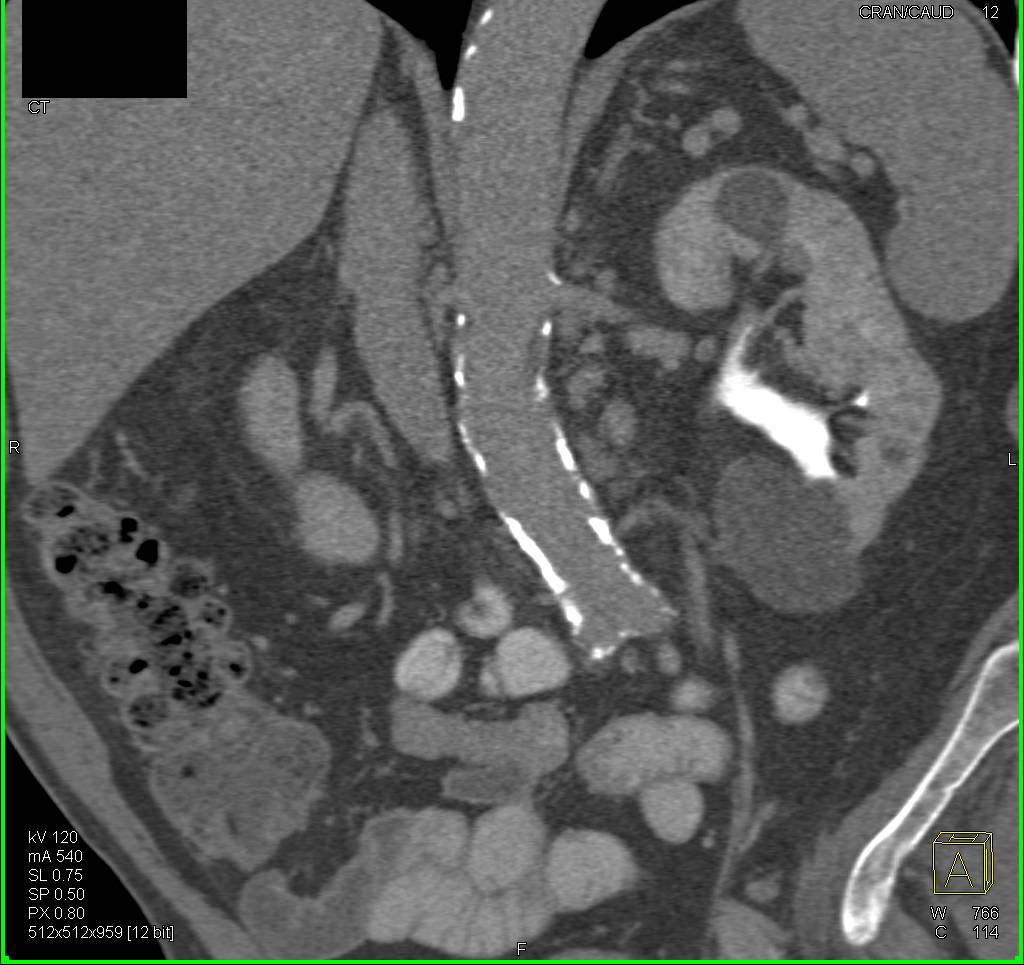

Diagnosis

Renal Cysts